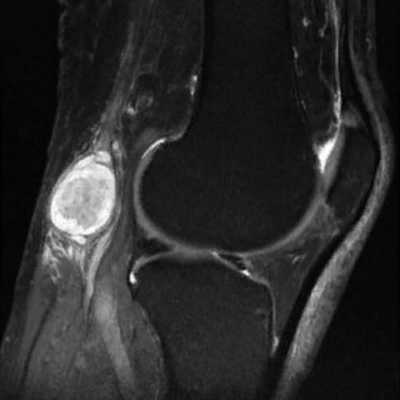

Как выглядит бурсит колена на снимке МРТ?

Коленный сустав защищают от повреждений несколько сумок

Препателлярный бурсит

Воспаление передней подкожной преднадколенниковой сумки на МРТ (стрелка)

Препателлярная бурса представляет собой трехкомпонентную структуру. Поверхностный отсек находится между подкожной клетчаткой и продолжением широкой фасции бедра, средний - между поперечной поверхностной и промежуточной косой фасциями. Глубокий ограничен косой соединительнотканной оболочкой и продольными волокнами сухожилия прямой мышцы бедра. Воспаление указанной синовиальной сумки происходит от длительного стояния на коленях, патологию регистрируют при подагре. Основные клинические проявления - боль и припухлость. Хроническая травматизация приводит к воспалению и геморрагическому бурситу. На МРТ препателлярный бурсит проявляется в виде овального жидкостного образования между подкожной клетчаткой и надколенником.